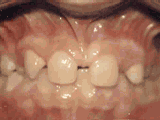

症状表现:牙齿缺失、牙周疾病等导致相邻牙齿无秩序前突。

症状表现:超出正常牙齿颗数,造成牙齿排列不齐,一般需要拔牙。

症状表现:牙齿过多,牙槽骨过窄,使牙齿没有足够空间生长就会造成牙齿排列不齐,需根据情况判断是否拔牙。